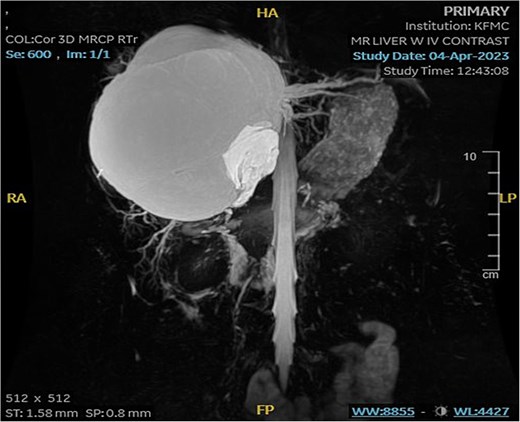

The mass had fine, minimally enhancing septations without any solid enhancing component. Communication with the right intrahepatic biliary ducts was observed, leading to moderate intrahepatic biliary duct dilatation. Magnetic resonance imaging (MRI) of the liver using contrast reveals a large hepatic cystic mass, corresponding to dimensions noted on CT, showing bright T2 signal intensity with thin septations without a solid component, illustrated in Fig. 2.

MRI of the liver: Demonstrating the mass in T2. Mild splenomegaly was noted without focal lesions. A) Transverse view, B) longitudinal view.

Mild splenomegaly (13.4 cm) with no focal lesions was noted, which exerted a mass effect on the patent hepatic vasculature. No osseous lesions or lymphadenopathies were identified. Three smaller bright T2 signal intensity lesions that did not enhance on post-contrast scanning were seen in segments 7 and 6, with measurements 0.2 × 0.1 cm, 0.7 × 0.7 cm, and 0.9 × 0.4 cm, respectively. The consistency of the cyst is evident from Fig. 3.